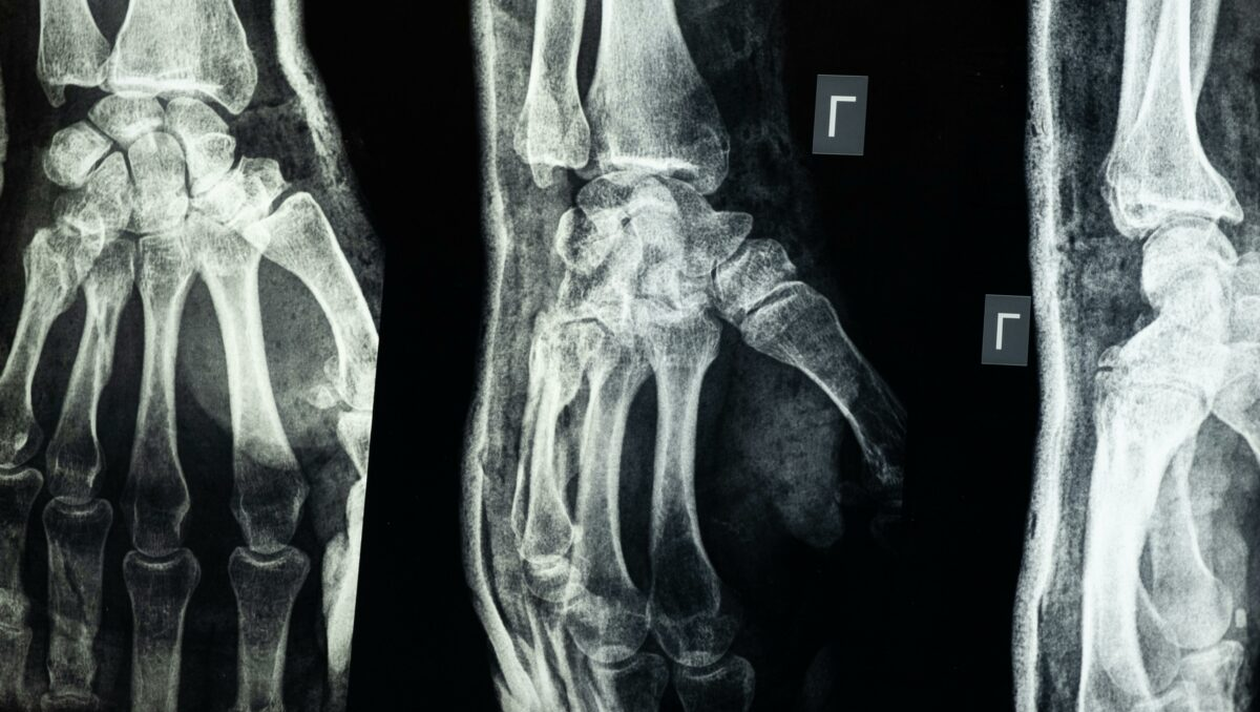

Oasele corpului uman, sursa-pexels.com

În același timp, aproximativ jumătate din toate oasele corpului se află în mâini și picioare, iar unele persoane pot avea oase accesorii, adică oase suplimentare mici rezultate din variații de dezvoltare, cum este cazul osului os trigonum din zona gleznei.